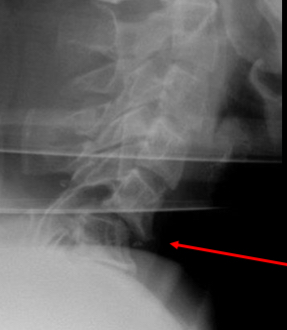

describe this radiograph

Anterior soft tissue measuring more

than 20mm at the level of C6.

• Indicates possible trauma.

• Patient has a tear-drop fracture of the

vertebral body of C3